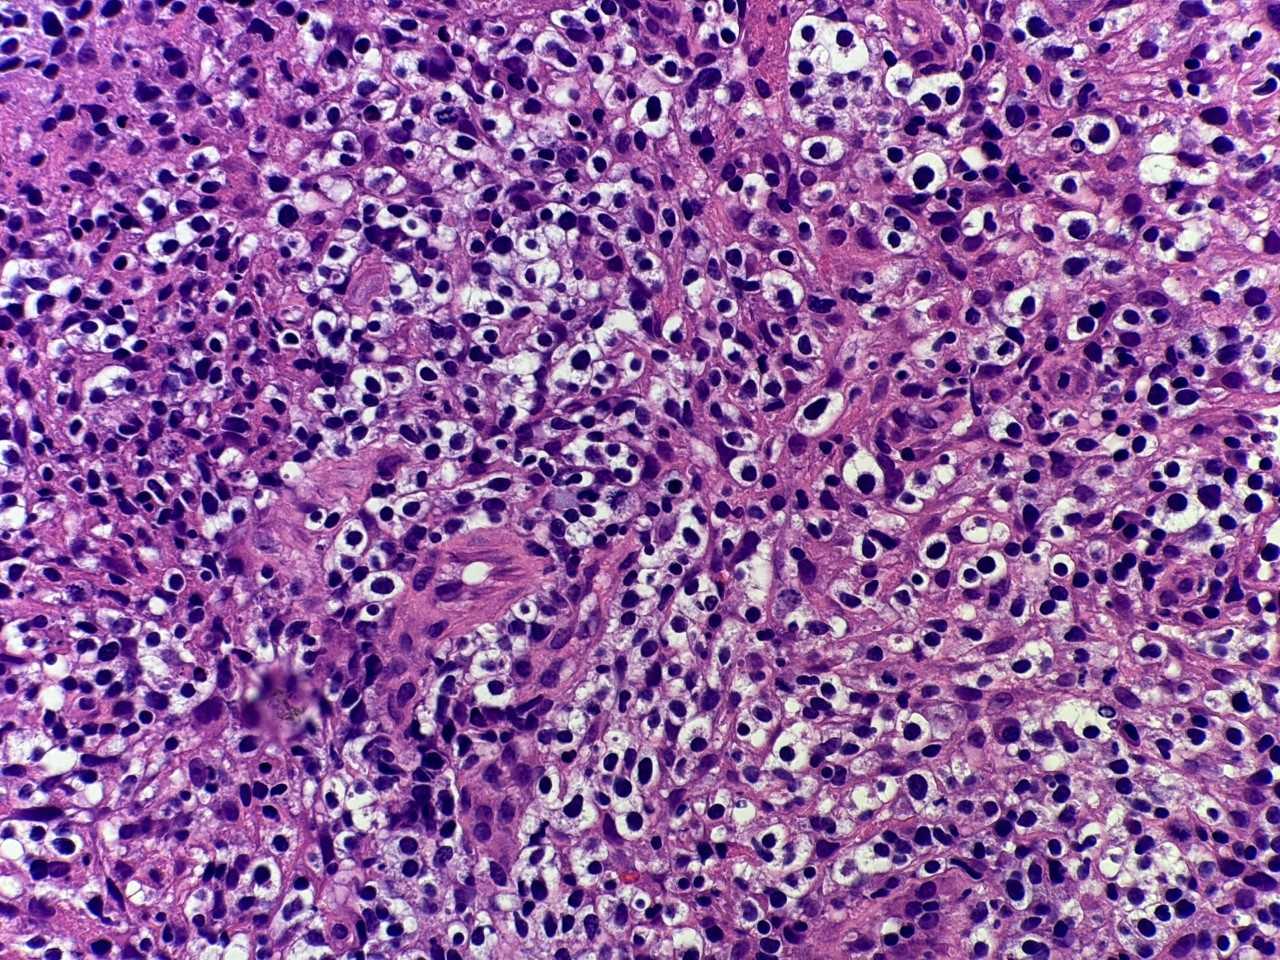

A 53-year-old female with acute hypoxic respiratory failure and pancytopenia. Imaging showed pulmonary infiltrates and lymphadenopathy. The morphology of a right axillary lymph node and immunohistochemical stains are shown.

The H&E section shows diffuse involvement by heterogenous atypical lymphocytes with moderate amounts of clear cytoplasm and prominent vascular proliferation. These cells are positive for CD4, CD2, CD3, CD5 and T-follicular helper markers including CD10, BCL6, ICOS and PD-1. Angioimmunoblastic T-cell lymphoma is a member of the T-follicular helper family of nodal T-cell lymphomas and is characterized by a T-cell infiltrate with expression of at least two T-follicular helper markers, high endothelial venule proliferation, and follicular dendritic network expansion.